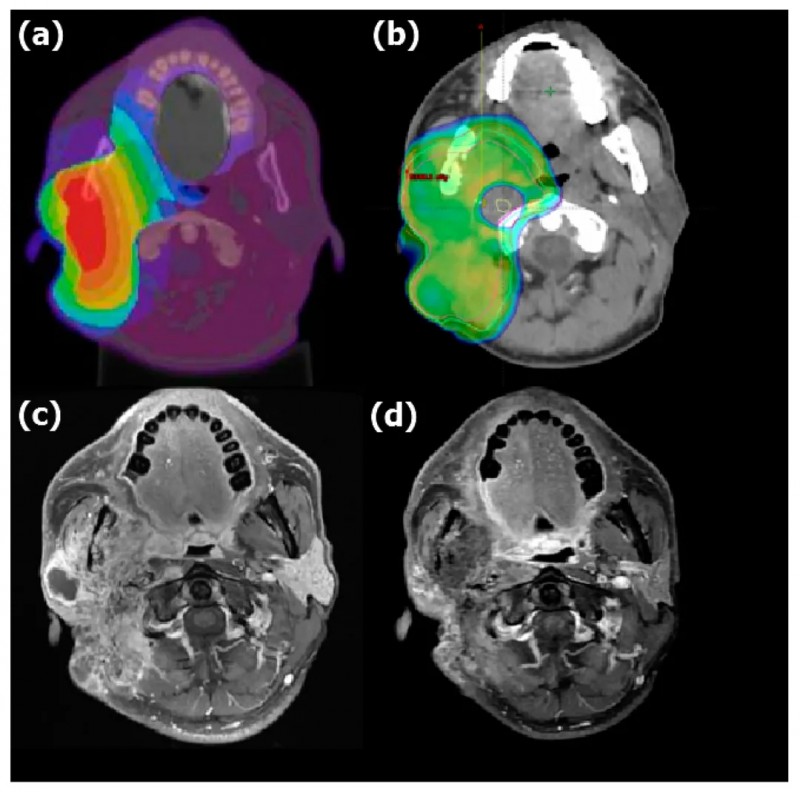

下图展示了一例复发性口腔癌患者,联合治疗前后的剂量分布对比,治疗后该患者肿瘤完全消失。

▲图源“Cancers”,版权归原作者所有,如无意中侵犯了知识产权,请联系我们删除

另一图则展示了一例右腮腺复发性粘液表皮样癌患者,联合治疗前后的剂量分布对比,治疗后患者肿瘤体积明显缩小。